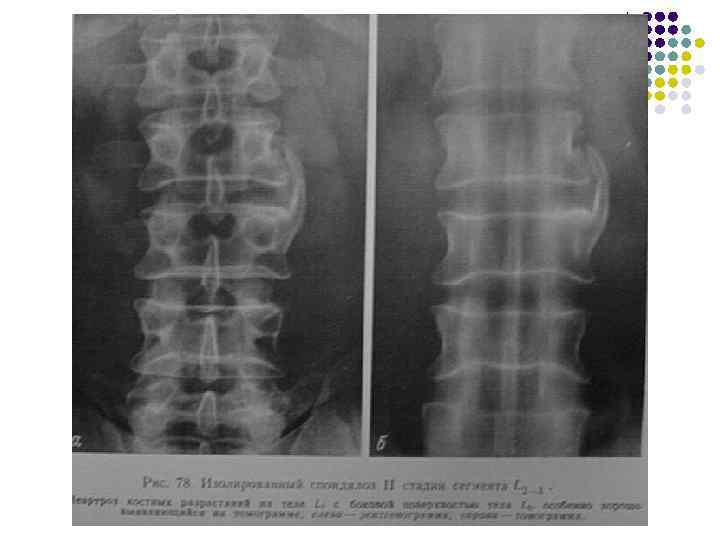

Спондилоз 1. 2. 3. Высота межпозвонкового диска не меняется. Обызвествления под передней продольной связкой начинаются над лимбусом и направлены вертикально. Нет субхондрального склероза поверхностей тел позвонков.

Стадии I стадия – обызвествление не выходит за уровень замыкающей пластинки позвонка II стадия – выход обызвествления за лимбус вплоть до тела смежного позвонка с образованием неоартрозов III стадия – слияние и фиксация позвонков подсвязочными обызвествлениями.